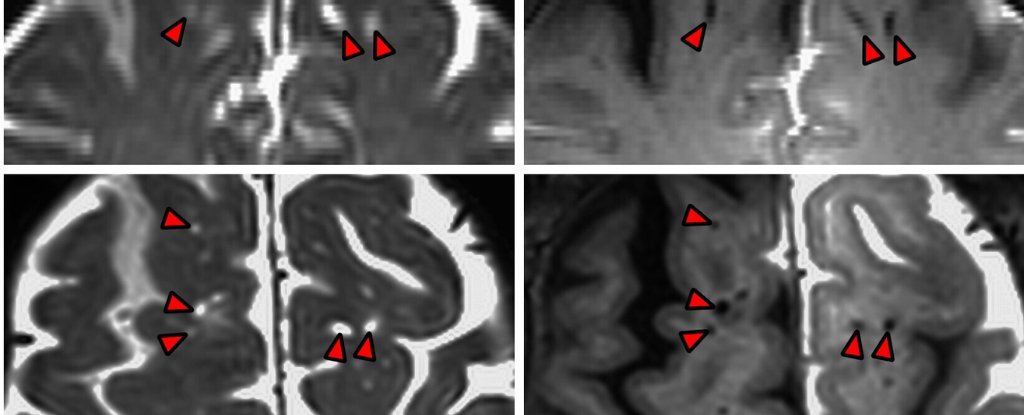

دانشمندان برای اولینبار سیستم دفع ضایعات مغز انسان را به عکس کشیدند_به رنگ صبح

نوشته و ویرایش شده توسط مجله به رنگ صبح کارکرد درونی سیستم دفع ضایعات مغز ما سرانجام بعد از سالها…